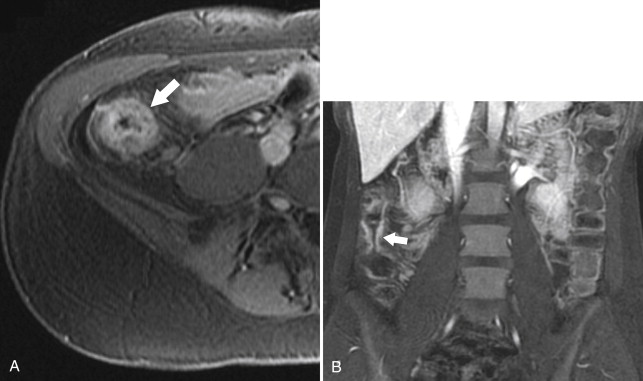

Ultrasound (US) sometimes shows a hypoechoic cystic mass with a thick wall, which has an echogenic outer layer and hypoechoic inner layer. On BE the cyst produces a mass effect of adjacent bowel and on CT appears as a nonenhancing mass, compressing or displacing the adjacent bowel, which may contain simple fluid, hemorrhage, or proteinaceous fluid ( Fig. 5-4 ). On MRI the enteric cysts are usually hyperintense on T2-weighted imaging, reflecting their cystic nature ( Fig. 5-5 ). Because many duplication cysts contain ectopic gastric mucosa, a Tc-99m pertechnetate radionuclide study can often show radionuclide uptake, which can also be observed within a Meckel diverticulum for the same reason.

Figure 5-4, Axial contrast-enhanced CT in a 46-year-old woman with a 4.5-cm homogeneous pararectal mass ( arrow ) caused by rectal enteric duplication.

Figure 5-5, Axial ( A ) and sagittal ( B ) T2-weighted imaging in a 30-year-old woman with a cystic 4.5-cm mass ( arrows ) in a posterolateral perirectal location resulting from a rectal duplication cyst.